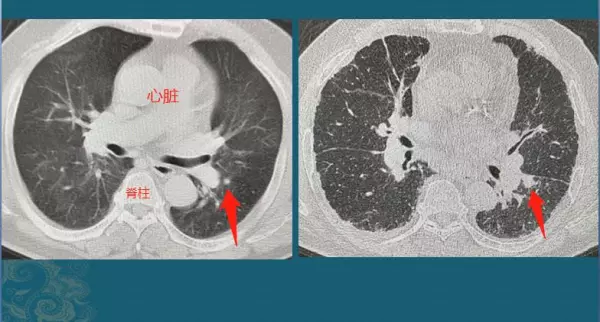

上图这位老年男性患者,因为头晕住院,胸部体检发现左下肺实性小结节,直径5mm,建议他3-6个月复查,结果老人的家属没有遵从指导,直到18个月后,老人出现胸痛、咳嗽症状才回来复查,结节增大到1.1cm,由于位置靠近叶间胸膜,癌细胞顺着胸膜上丰富的脉管系统转移了,没有根治机会了……